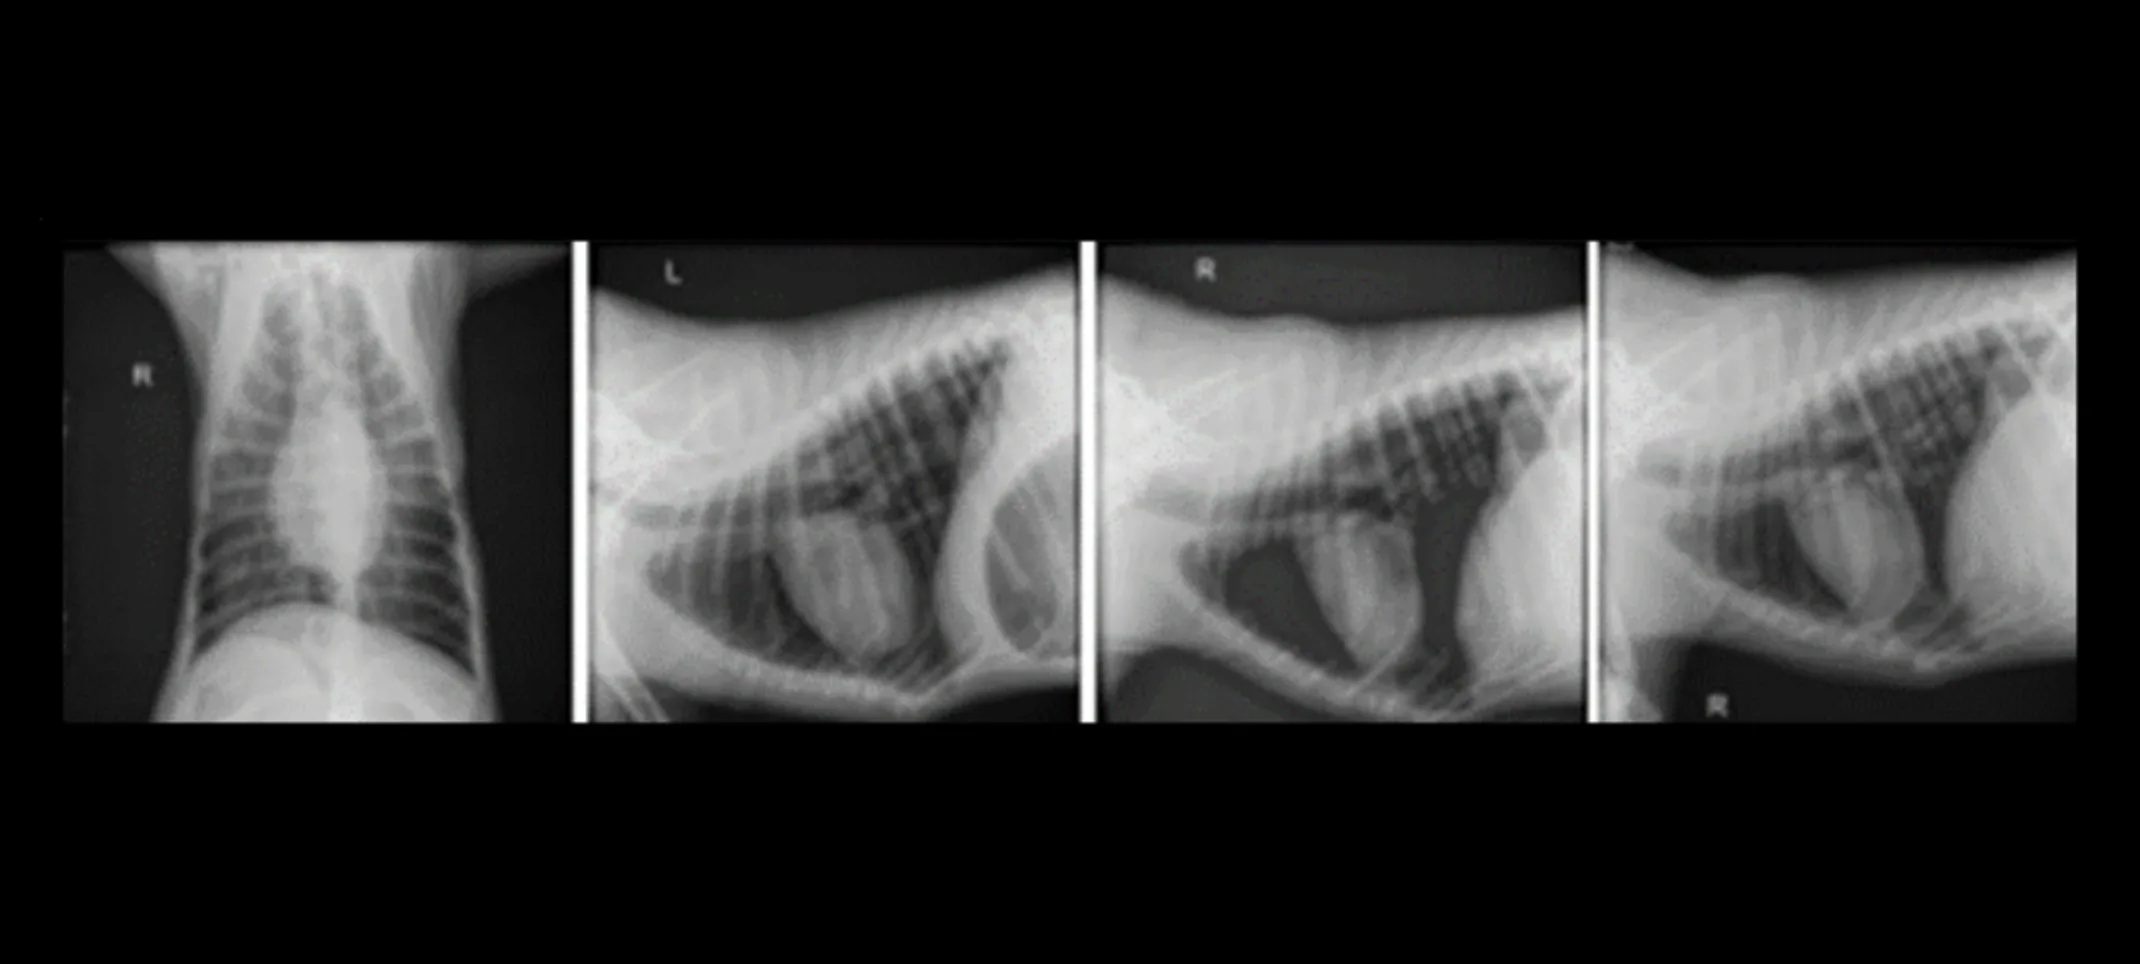

A comprehensive physical examination by Dr. Rachel Orlowski and subsequent diagnostic tests led to a swift diagnosis of Gastric Dilatation-Volvulus (GDV). X-rays were critical in confirming GDV, revealing the classic "double bubble" sign, a definitive indicator of this condition, where the stomach appears divided into separate gas-filled segments. This x-ray finding was essential in diagnosing the severity of the gastric torsion and underlined the urgent need for surgical intervention.

Imaging: Thorax imaging was performed to evaluate the overall health of the chest and rule out other complications that could render Riggins a less suitable candidate for surgery, such as severe cardiopulmonary issues that could complicate anesthesia and recovery. issues that could complicate anesthesia and recovery.